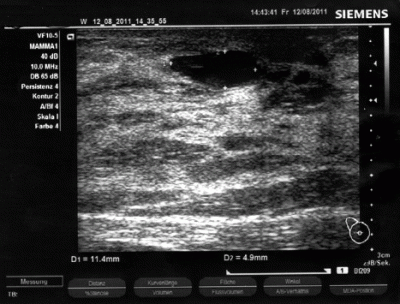

Mammazyste während der Punktion

Mammazyste nach der Punktion